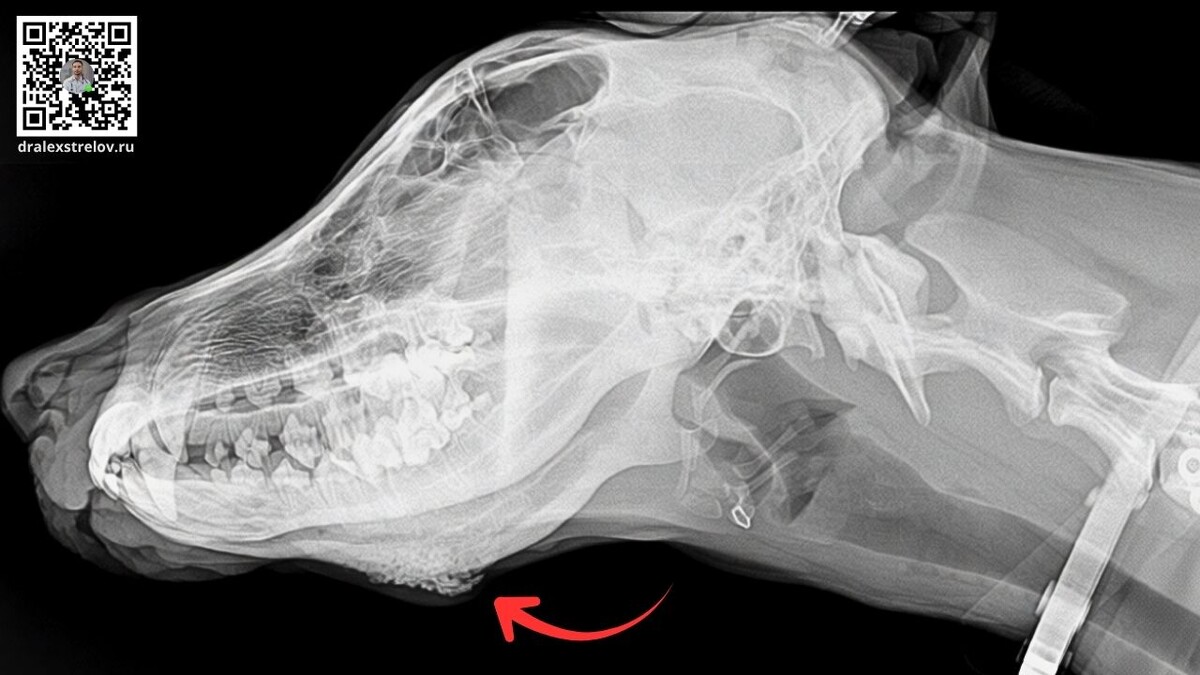

Два врача — два диагноза: злокачественная опухоль или воспаление?

Молодая среднеазиатская овчарка с образованием на челюсти. Первый врач сказал: остеосаркома. Второй — гипертрофическая остеодистрофия, назначил преднизолон. Через две недели лечения образование выросло ещё больше.

Главный урок этого случая: когда речь о подозрении на рак кости, рентген не даёт окончательного ответа. Только биопсия может разрешить диагностическую неопределённость и показать истинную природу процесса.

Нетипичная локализация для воспаления, отсутствие ответа на терапию, быстрый рост — всё указывало на онкологию. Но без гистологии это были лишь предположения.